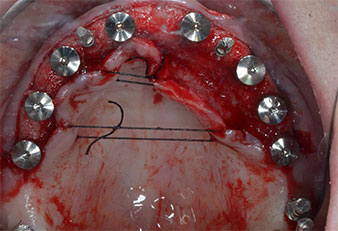

Three years later it was time for a maxillary denture of the same type. Based on CBCT planning sinus augmentation was avoided with the aid of short implants, and a surgical template was used to transfer the planned positions to the alveolar ridge (Figs. 1 and 2).

Fig. 1: Pre-operative view of the maxillary ridge, with implant positions marked with the aid of a surgical plastic template. Due to the low ridge super short posterior implants are planned.

Implant positions

Fig. 2: After mid-crestal incision and preparation of mucoperiosteal flaps the implant positions are transferred to the bone.